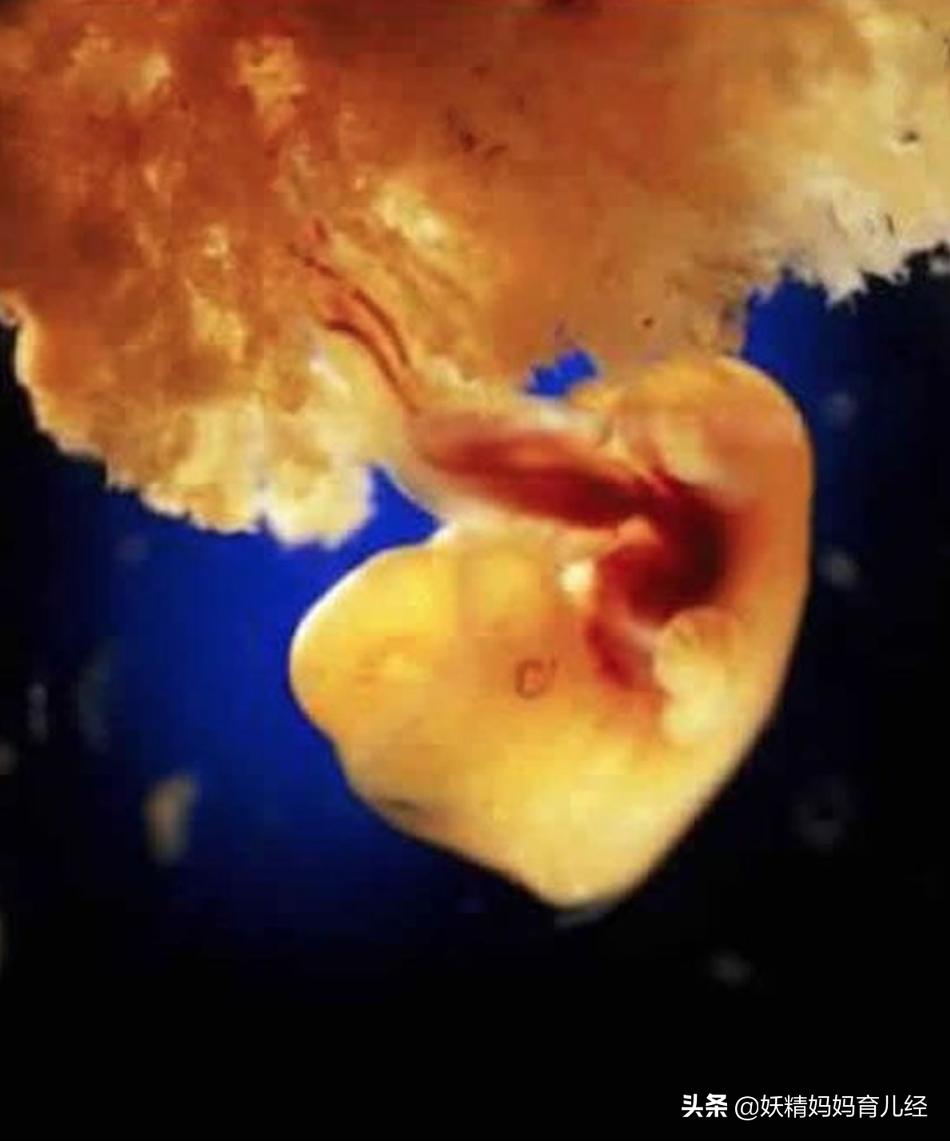

8、怀孕后的第四周,胎儿还没有发育骨骼,但是你的身体里多了一个人的心跳。咚咚咚。

9、怀孕第四周,胎儿长出了手脚。